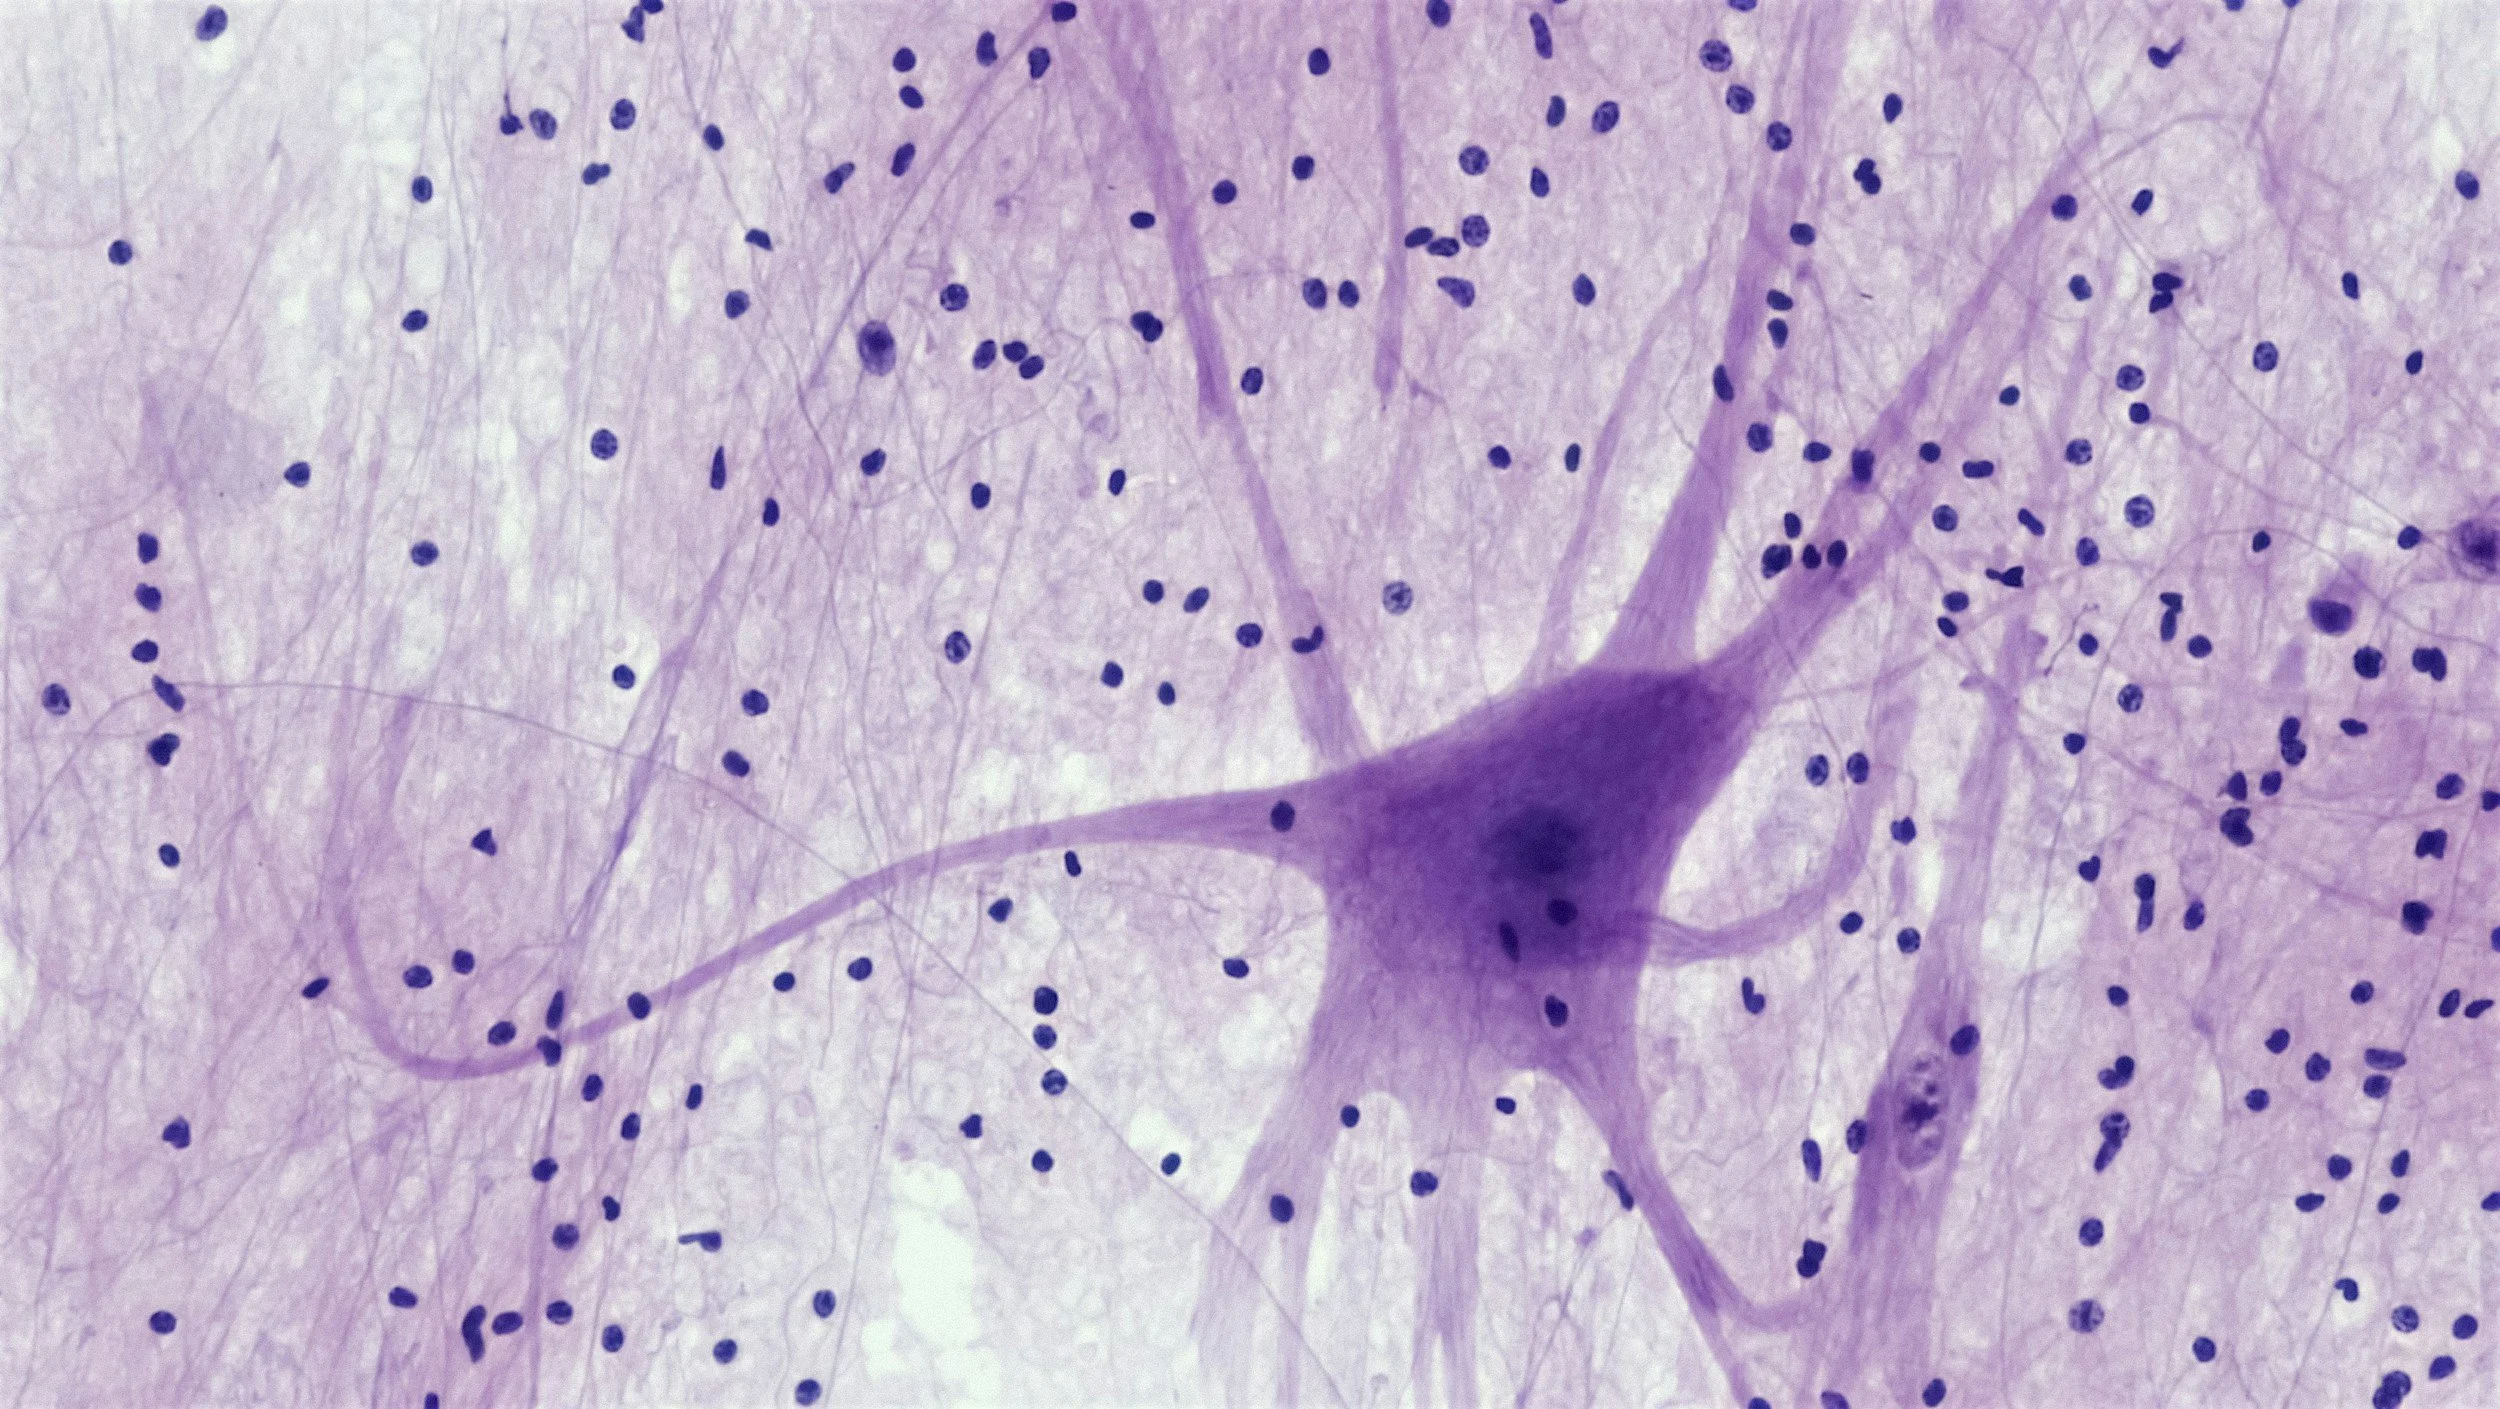

De nombreuses recherches en neurosciences et psychoneuroimmunologie confirment aujourd’hui que :

Le corps conserve la trace de nos expériences passées à travers le système nerveux,

Les émotions influencent la tonicité musculaire, la respiration, la posture et même l’expression génétique (épigénétique),

Certaines réactions sont hors du champ conscient mais restent actives dans le corps (mémoire implicite, somatique).

Le test musculaire agit alors comme une interface pour accéder à cette mémoire cellulaire. Il donne une indication subtile mais fiable sur ce qui stresse le corps ou, au contraire, le renforce.